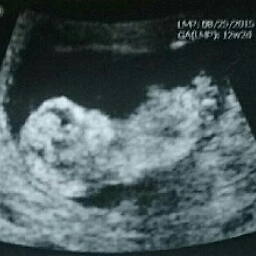

This is for my sister in law. Any guesses would be appreciated :)Attachment 29203

Blurry but maybe boy, what gestation was she :)

more pics? Veeery slight girly lean